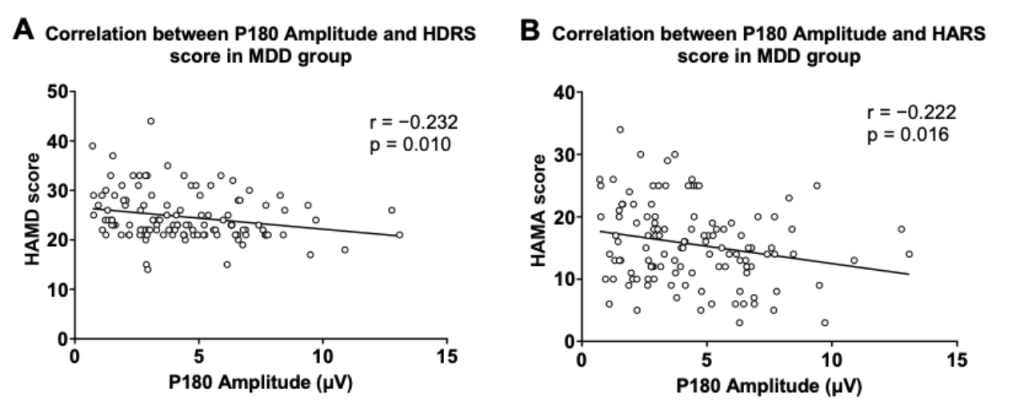

圖1分別顯示了健康對照組與患者組的TMS誘發腦電的蝴蝶圖。研究結果顯示,抑郁癥患者P180波幅顯著低于健康對照人群。在抑郁癥患者中,P180波幅與抑郁、焦慮癥狀得分呈顯著負相關;P30波幅與RBANS視覺空間/結構得分和總分呈顯著負相關。

多元回歸分析表明,P180波幅能負向預測患者的抑郁及焦慮癥狀;P30波幅、發病年齡和教育程度能負向預測患者的認知功能。

圖2. P180波幅與抑郁及焦慮癥狀得分的關系